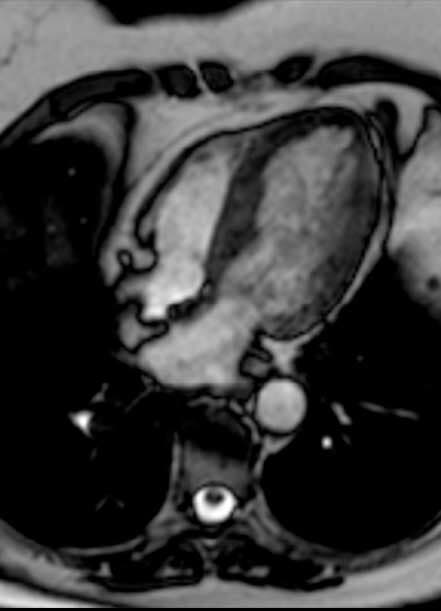

- Resonancia magnética

- Resonancia magnética de corazón

- Imagen cardiovascular